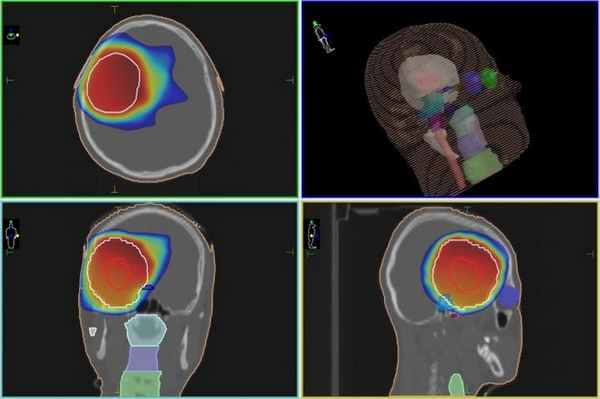

Протонная терапия, план лечения астробластомы. Зона, указанная синим и зеленым цветом, получит высокую дозу ионизируюшего излучения, гибельного для опухоли. Остальной мозг – защищен от радиации благодаря точности метода протонной терапии и высокой квалификации врачей МИБС.

Екатерина Бычковская болеет с начала 2018 года. При обследовании по данным МРТ выявлена опухоль мозга в левой лобной доле диаметром 6,5 см. После хирургического удаления был проведен гистологический анализ, заключение – Астробластома, Grade IV.

Учитывая гистологический диагноз, возраст пациента, выполненную резекцию опухоли, рекомендовано проведение лучевой терапии на область опухоли и параллельно – химиотерапии. Ввиду юного возраста и локализации опухоли предпочтительным методом лучевой терапии является протонная терапия.

В МИБС девочке проведен курс лучевой протонной терапии на ложе удалённой опухоли с применением установки Pro Beam. В конце апреля пациентка выписана для проведения следующего этапа лечения астробластомы, дома, в Республике Беларусь.